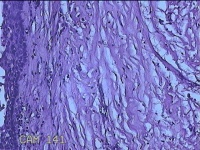

左上后牙根尖肿物

性别

男

年龄

42岁

临床诊断

慢性牙周炎

一般病史

左上后牙残根邀请拔除。

标本名称

大体所见

灰白暗红色肿物1.5x0.8x0.3cm一个,表面光滑,切开肿物呈囊性,囊内有大量脓液,囊壁厚0.2ml,另有牙齿1.5x0.8x0.7cm一颗。